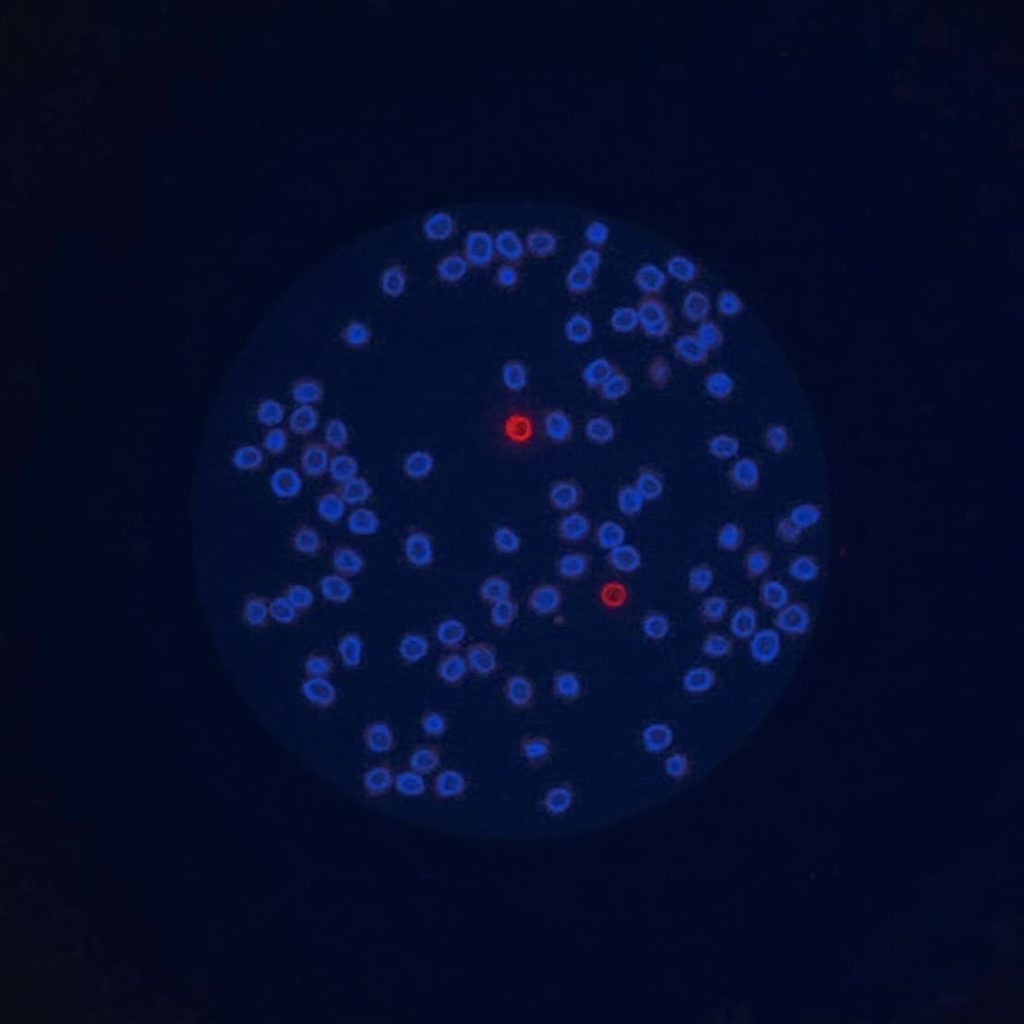

MDA-MB-231 cells are important for studying triple-negative breast cancer (TNBC). This type of breast cancer is hard to treat because